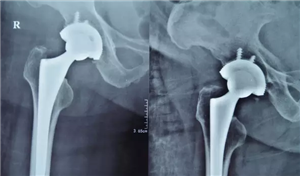

(术后)

2016年10月12日,胡玉华院长、李龙付副主任为老奶奶实施了“右侧人工髋关节置换术”,一个半小时的手术很成功。术后,老人被送入ICU进行术后的监护。